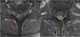

Metastasis to spine

Bone metastases, or osseous metastatic disease, is a category of cancer metastases that results from primary tumor invasion to bone. Bone-originating primary tumors such as osteosarcoma, chondrosarcoma, and Ewing's sarcoma are rare. [Source: Wikipedia ]